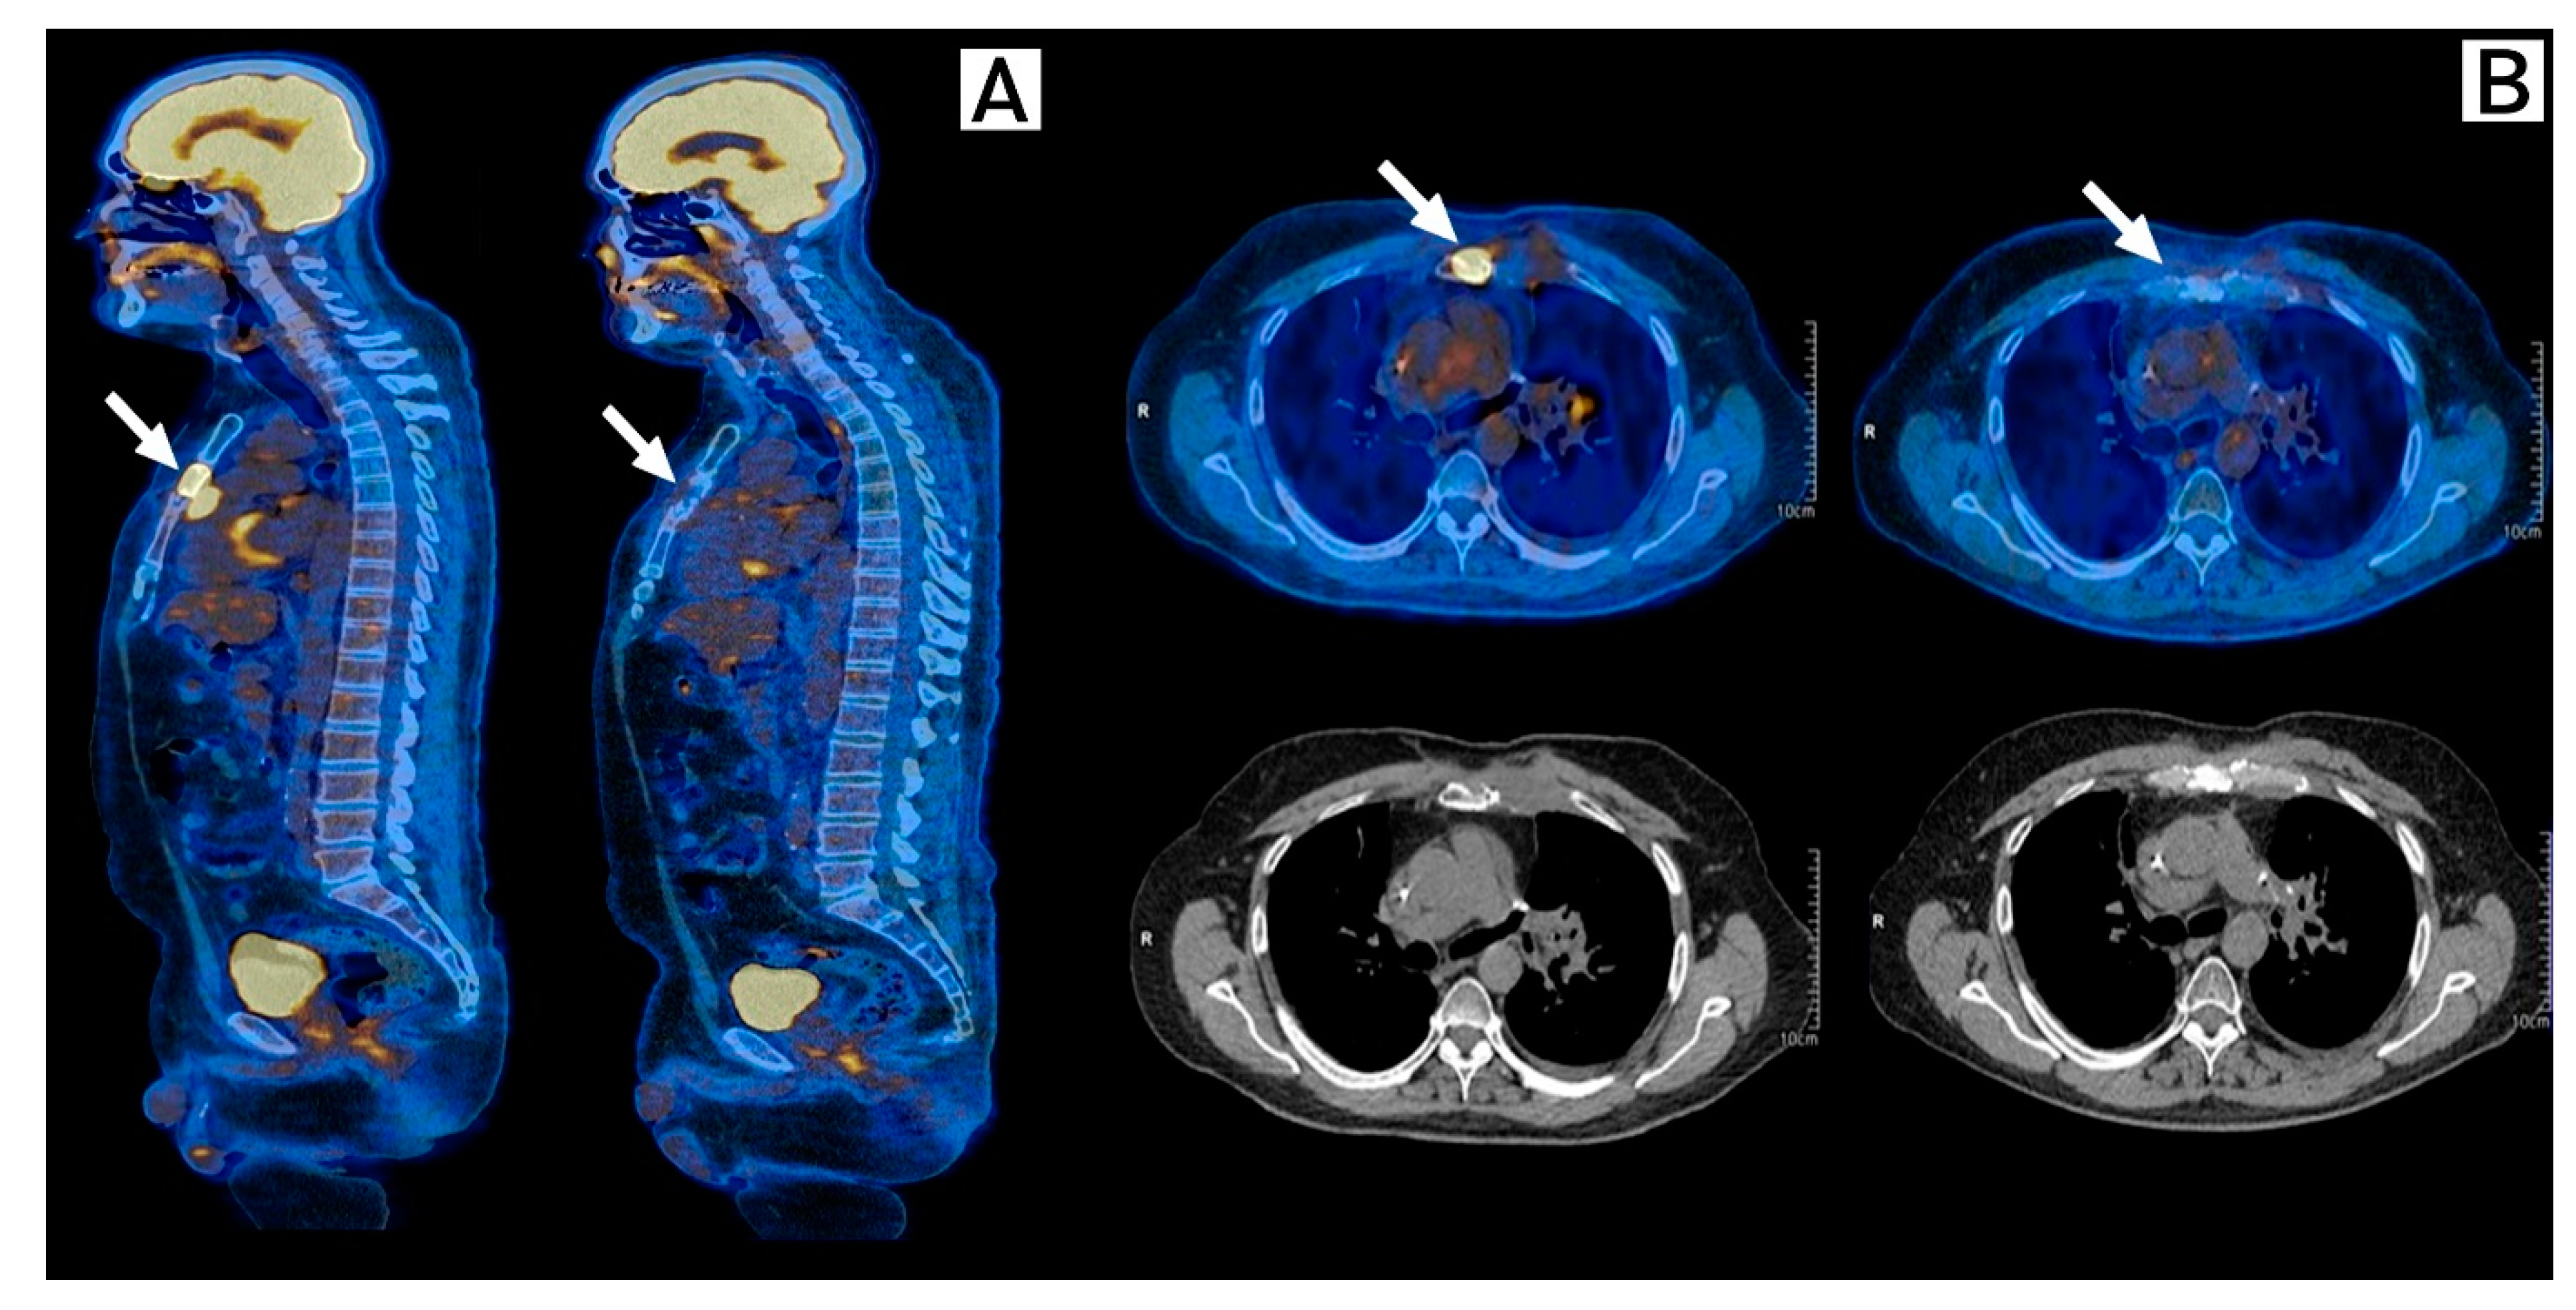

In July 2021, after full recovery from pneumonitis and having remained with no cancer treatment for 3 months and still having measurable disease, an immunotherapy rechallenge was recommended. He received two cycles of Ipilimumab 1 mg/kg plus Nivolumab 3 mg/kg, followed by maintenance with Nivolumab 240 mg q2w. In January 2022, a new PET-CT showed a partial response and complete metabolic response to immunotherapy rechallenge (Figure 4). The patient is still on maintenance nivolumab, sustaining a durable response confirmed by a PET-CT performed in October 2022.

Figure 4.

Response to immunotherapy rechallenge. FDG-PET-Scan, Baseline (left) and 6 months after (right) after initiation of Ipilimumab plus Nivolumab. (A) Sagittal plane, and (B) Transversal plane. Arrows show a partial response with metabolic response of sternum and costochondral lesions when compared to prior scans, demonstrating a response to Ipilimumab plus Nivolumab.